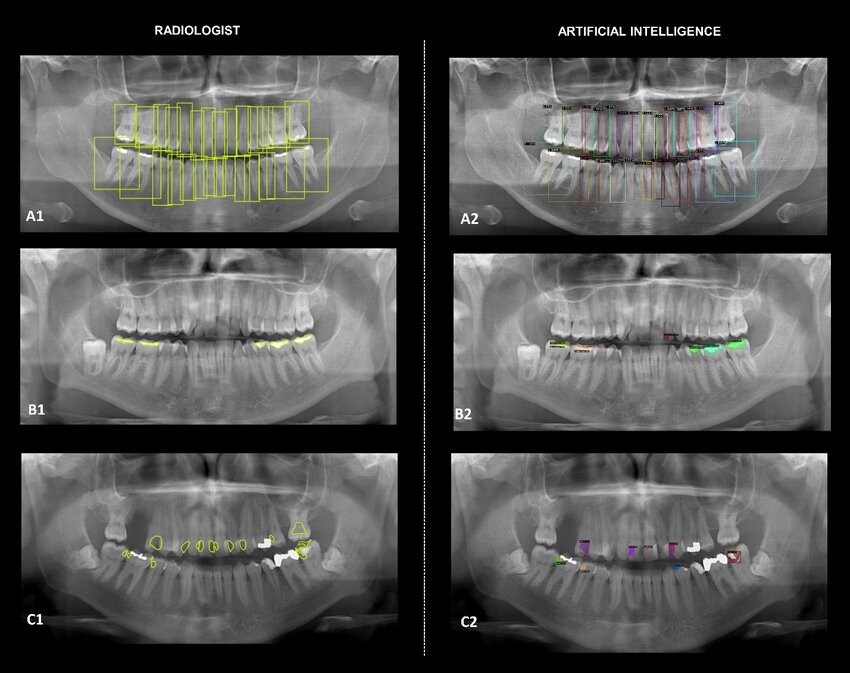

How to build yolov8 dental object detection model / Object Detection, Pytorch Contents hide 1 Getting started with YOLOv8 dental object detection 2 Why yolov8 dental object detection is worth learning 3 Walking through our YOLOv8 dental object detection tutorial 3.1 Master Computer Vision 4 Walking through our YOLOv8 dental object detection tutorial 5 Setting up the environment for YOLOv8 dental object detection 6 Organizing the dental dataset for YOLOv8 7 Visualizing a labeled dental X-ray with bounding boxes 8 Training the YOLOv8 dental object detection model 9 Running predictions and comparing with ground truth 10 FAQ: Yolov8 dental object detection 10.1 What is yolov8 dental object detection? 10.2 Do I need CUDA and a GPU for this tutorial? 10.3 Which label format does the code expect? 10.4 Where does YOLOv8 save the best model weights? 10.5 How can I verify my dental labels are correct? 10.6 Can I add more dental classes like implants or crowns? 10.7 What should I do if training is too slow? 10.8 How do I handle CUDA out of memory errors? 10.9 Can I reuse this pipeline for other medical images? 10.10 How do I know if my model is good enough? 11 Conclusion 11.1 Connect : Last Updated on 22/04/2026 by Eran Feit Getting started with YOLOv8 dental object detection In modern dentistry, X-rays are no longer just static images on a screen. With yolov8 dental object detection, those images can be transformed into structured data that highlights teeth, restorations, lesions, and other findings automatically. Instead of manually scanning every millimeter of a radiograph, a trained YOLOv8 model can detect relevant structures in a single pass, drawing bounding boxes and assigning labels in real time. YOLOv8 is a state-of-the-art object detection framework designed for speed and accuracy, which makes it well suited for clinical and research scenarios where both reliability and performance matter. By learning from annotated dental X-rays, YOLOv8 can adapt to the unique contrast patterns, artifacts, and anatomy present in panoramic, bitewing, and periapical images. This allows it to generalize across different patients, imaging devices, and acquisition settings while maintaining strong detection performance. When applied to dental imaging, YOLOv8 dental object detection can support tasks such as tooth numbering, identifying missing or impacted teeth, flagging potential caries, and detecting existing restorations. Models trained on large, well-labeled datasets have achieved high precision and recall in identifying permanent and deciduous teeth across multiple X-ray types, demonstrating that deep learning can complement the expertise of dentists rather than replace it. A typical workflow starts with collecting and labeling a dataset of dental X-rays, defining the objects of interest (for example, individual teeth or specific conditions), and configuring a data file that YOLOv8 can read. From there, you train the model using a GPU-enabled Python environment, monitor metrics like mAP and F1-score, and refine the training setup as needed. Once the model is ready, you run inference on new X-rays and visualize the results with bounding boxes overlaid on the images to compare predictions with ground truth or clinician annotations. Teeth Detection using Yolo V8 If you enjoy building custom detectors like this, you might also like my How to Train YOLOv5 on a Custom Dataset tutorial for another end-to-end object detection pipeline. Why yolov8 dental object detection is worth learning Yolov8 dental object detection is valuable because it brings consistent, repeatable analysis to an area that traditionally relies on manual inspection. Even experienced clinicians can have subtle differences in how they interpret radiographs, especially when dealing with large volumes of images. A well-trained YOLOv8 model applies the same criteria every time it processes an X-ray, which can help with standardizing documentation, tracking changes over time, and supporting decision-making. Another strength of YOLOv8 in dental applications is its efficiency. The model is designed as a one-stage detector, which keeps inference times low enough for potential real-time use in clinics. That means dental practices and research labs can integrate object detection into their workflows without adding significant delays, whether they are running batch analyses of epidemiological datasets or providing instant feedback during patient consultations. From a development perspective, working with yolov8 dental object detection is approachable for anyone familiar with Python and basic deep learning concepts. You can set up a conda environment, install PyTorch and Ultralytics YOLO, download an annotated dental dataset, and start training a custom model in relatively few steps. The configuration files are human-readable, and the training API exposes parameters like epochs, batch size, and image size, giving you fine-grained control over the learning process. Finally, this type of model opens the door to more advanced pipelines. Once you can reliably detect teeth and other structures, you can extend the system to segmentation, measurement, or even automated reporting that summarizes findings in natural language. Combined with clinical expertise, yolov8 dental object detection becomes a foundation for intelligent tools that improve efficiency, support early detection of problems, and enhance communication with patients. YoloV8 dental object detection Walking through our YOLOv8 dental object detection tutorial This tutorial walks you step by step through a complete yolov8 dental object detection pipeline, from a blank environment to a trained model that can detect teeth on X-ray images.The code is written in Python and uses a combination of Conda, PyTorch, the Ultralytics YOLOv8 package, OpenCV, and a labeled dental dataset from Roboflow.The goal is that you can copy the code into your own environment, make small path adjustments, and quickly reproduce the same results on your machine. The first part of the code focuses on setting up a clean working environment.You create and activate a Conda environment, install the correct CUDA-enabled PyTorch version, and then install YOLOv8 from Ultralytics.This ensures that GPU acceleration works out of the box and that your training loop will run efficiently on modern hardware. Next, the tutorial code prepares the data.You download a dental X-ray dataset, organize the images and YOLO-format label files into train and validation folders, and load the data.yaml configuration to read the class names.There is also a dedicated section that loads a single image and its label file, converts YOLO coordinates to pixel coordinates, and uses OpenCV to draw bounding boxes and class names.This small visualization step is crucial, because it lets you verify that the annotations are correct before investing time in model training. The core of the script is the training function.Here, you initialize a YOLOv8 model from a configuration file (for example, yolov8l.yaml), point it to your data.yaml, and launch training with parameters such as number of epochs, batch size, project folder, and experiment name.YOLOv8 handles the full training loop, saving metrics and model weights (including best.pt) into a well-organized results directory that you can revisit later. Finally, the last part of the tutorial loads the trained model and runs inference on a test image.The code draws predicted bounding boxes and labels on a copy of the original X-ray, and then reconstructs the ground-truth boxes from the label file for side-by-side comparison.By saving and displaying both images, you can visually inspect how well the YOLOv8 model learned to perform dental object detection and decide whether you want to fine-tune, add more data, or move on to integrating the model into a larger application. For more practice with custom datasets, take a look at How to Train Detectron2 on Custom Object Detection Data , where we register COCO-style annotations and train a flexible Detectron2 model. Link to the video tutorial here You can download the code here : https://eranfeit.lemonsqueezy.com/buy/10f89403-68e0-4929-be6e-79e4ce9682e7 or here : https://ko-fi.com/s/1479347c90 Link for medium users : https://medium.com/object-detection-tutorials/how-to-build-yolov8-dental-object-detection-model-07ee6ee36296 TRY IT NOW Master Computer Vision Follow my latest tutorials and AI insights on my Personal Blog. Beginner Complete CV Bootcamp Foundation using PyTorch & TensorFlow. Get Started → Interactive Deep Learning with PyTorch Hands-on practice in an interactive environment. Start Learning → Advanced Modern CV: GPT & OpenCV4 Vision GPT and production-ready models. Go Advanced → Walking through our YOLOv8 dental object detection tutorial This tutorial shows how to build a complete yolov8 dental object detection pipeline using Python.You start from a clean Conda environment and finish with a trained YOLOv8 model that can detect teeth on dental X-rays. The goal is to make each step copy-paste friendly so you can focus on understanding what the code does.You will see how to install the right libraries, organize your dental X-ray dataset, train the model, and visualize results with OpenCV. Along the way, you will also learn how YOLO format labels work, how to convert normalized coordinates into pixel coordinates, and how to compare predictions with ground truth boxes.These skills are reusable for any custom object detection project, not only dental images. By the end of this post, you will have a practical workflow for yolov8 dental object detection that you can reuse on other medical or industrial datasets.You can then extend the same pattern to more tooth classes, different pathologies, or even other imaging modalities. If you want a complete YOLOv8 YouTube object detection workflow (auto-labeling, training, and live inference), follow this step-by-step guide: https://eranfeit.net/how-to-use-yolov8-for-object-detection-on-youtube-videos/ Setting up the environment for YOLOv8 dental object detection Before training a model, you need a clean Python environment with compatible versions of CUDA, PyTorch, and YOLOv8.Here you will create a Conda environment, install GPU-enabled PyTorch, and add the Ultralytics package. ### Create a new Conda environment for the YOLOv8 dental project. conda create --name YoloV8 python=3.8 ### Activate the environment so all packages are isolated from your base setup. conda activate YoloV8 ### Check that the NVIDIA CUDA compiler is installed and on your PATH. nvcc --version ### Install PyTorch, TorchVision, and Torchaudio with CUDA 11.8 support from the official channels. conda install pytorch==2.1.1 torchvision==0.16.1 torchaudio==2.1.1 pytorch-cuda=11.8 -c pytorch -c nvidia ### Install the Ultralytics package that provides the YOLOv8 implementation. pip install ultralytics==8.1.0 After running these commands, you have a dedicated environment that is ready for yolov8 dental object detection experiments.Keeping YOLOv8 and PyTorch in their own Conda env helps avoid version conflicts with other projects. Organizing the dental dataset for YOLOv8 YOLOv8 expects your images and labels to be organized in a consistent folder structure.Each image in the training, validation, and test sets has a matching text file with YOLO-format bounding boxes. A typical layout for this dental project looks like this. data/ train/ images/ labels/ valid/ images/ labels/ test/ images/ labels/ data.yaml The data.yaml file describes where the images live and which classes the model should learn.For a simple tooth detection task, it might contain a single class such as "tooth" or several classes if you distinguish between different tooth types. Once this structure is in place, YOLOv8 can iterate over your dental images, read the labels, and optimize the yolov8 dental object detection model without confusion.Verifying that paths and filenames match exactly will save you a lot of debugging time later. Visualizing a labeled dental X-ray with bounding boxes Before training, it is smart to verify that your YOLO labels actually line up with the teeth on the image.This script loads one dental image, reads the corresponding label file, converts YOLO coordinates to pixel coordinates, and draws bounding boxes with OpenCV. ### Import YOLO class from the Ultralytics package so we can work with YOLOv8 models. from ultralytics import YOLO ### Import OpenCV for reading images and drawing bounding boxes. import cv2 ### Import yaml to read the dataset configuration and class names. import yaml ### Path to a sample training image with dental annotations. img = "C:/Data-sets/teeth2/train/images/IMG_2135_JPG.rf.b7605f894721641aca14678cbdc8b2f7.jpg" ### Path to the corresponding YOLO label file for that image. imgAnotation = "C:/Data-sets/teeth2/train/labels/IMG_2135_JPG.rf.b7605f894721641aca14678cbdc8b2f7.txt" ### Path to the YOLOv8 data configuration YAML that contains class names and dataset paths. data_yaml_file = "C:/Data-sets/teeth2/data.yaml" ### Open the YAML file in read mode so we can parse it. with open(data_yaml_file, 'r') as file: ### Load the YAML content into a Python dictionary. data = yaml.safe_load(file) ### Extract the list of class names from the configuration. label_names = data['names'] ### Print the class names to confirm the config is loaded correctly. print(label_names) ### Read the dental X-ray image from disk. img = cv2.imread(img) ### Get the image height, width, and number of channels. H, W, _ = img.shape ### Open the YOLO label file and read all of its lines. with open(imgAnotation, 'r') as file: lines = file.readlines() ### Prepare an empty list to store parsed annotation tuples. annotations = [] ### Loop over each line and parse the YOLO annotation. for line in lines: ### Split the line into class ID and normalized box coordinates. values = line.split() ### The first value is the class label ID. label = values[0] ### The remaining values are center x, center y, width, and height in YOLO format. x, y, w, h = map(float, values[1:]) ### Add the parsed annotation as a tuple to the list. annotations.append((label, x, y, w, h)) ### Print the parsed annotations to verify they were read correctly. print(annotations) ### Loop over each annotation and draw the bounding box on the image. for annotation in annotations: ### Unpack the label and YOLO coordinates. label, x, y, w, h = annotation ### Convert the class ID into a human-readable label name. label_name = label_names[int(label)] ### Convert YOLO normalized coordinates into absolute pixel coordinates. x1 = int((x - w / 2) * W) y1 = int((y - h / 2) * H) x2 = int((x + w / 2) * W) y2 = int((y + h / 2) * H) ### Draw a green bounding box around the detected tooth. cv2.rectangle(img, (x1, y1), (x2, y2), (0, 255, 0), 1) ### Put the class name slightly above the bounding box. cv2.putText(img, label_name, (x1, y1 - 5), cv2.FONT_HERSHEY_COMPLEX, 0.5, (0, 255, 0), 1, cv2.LINE_AA) ### Save the visualization to disk so you can inspect it later. cv2.imwrite("c:/temp/1.png", img) ### Show the image in a window. cv2.imshow("img", img) ### Wait for a key press before closing the window. cv2.waitKey(0) If the boxes sit neatly on top of the teeth, your labels are correct and you can move on to training.If they are shifted or scaled incorrectly, check your image sizes, label paths, and any preprocessing steps before continuing. Training the YOLOv8 dental object detection model Now you are ready to train the yolov8 dental object detection model on your custom dataset.This script loads a YOLOv8 architecture, points it to the data.yaml file, and launches the training process with chosen hyperparameters. ### Import the YOLO class from Ultralytics so we can create and train models. from ultralytics import YOLO ### Define the main entry point of the training script. def main(): ### Load a YOLOv8 model architecture from its YAML configuration file. model = YOLO("yolov8l.yaml") ### Path to the data configuration file that describes our dental dataset. config_file_path = "C:/Data-sets/teeth2/data.yaml" ### Define the root folder where YOLOv8 will store all training outputs. project = "C:/Data-sets/teeth2" ### Give a name to this specific experiment so results go into a dedicated subfolder. experiment = "My-Teeth-Model" ### Set the training batch size to control how many images run in parallel on the GPU. batch_size = 16 ### Launch the training process with our configuration and hyperparameters. results = model.train( data=config_file_path, epochs=100, project=project, name=experiment, batch=batch_size, device=0, val=True, ) ### After training, results and weights will be saved under project/experiment. print(results) ### Make sure main() runs only when this script is executed directly. if __name__ == "__main__": main() During training, YOLOv8 logs metrics such as loss and mean average precision so you can track how well the model is learning.The best weights are saved under C:/Data-sets/teeth2/My-Teeth-Model/weights/best.pt, which you will use for inference on new dental X-rays. If you want to compare YOLOv8 with other modern detectors, you can follow my Getting Started with YOLOX for Object Detection and SSD MobileNet v3 Object Detection Explained for Beginners guides. Running predictions and comparing with ground truth Once training is complete, you can load the best checkpoint and run yolov8 dental object detection on test images.This script draws both the predicted bounding boxes and the ground truth boxes so you can visually compare how well the model performs. ### Import the YOLO class to load the trained model for inference. from ultralytics import YOLO ### Import OpenCV for image handling and drawing results. import cv2 ### Import os to help build file paths in a platform-independent way. import os ### Path to a test dental X-ray image. imgTest = "C:/Data-sets/teeth2/test/images/IMG_5623_JPG.rf.0c498b907e44fe1bdba6ee17166bee3e.jpg" ### Path to the ground truth YOLO label file for that test image. imgAnot = "C:/Data-sets/teeth2/test/labels/IMG_5623_JPG.rf.0c498b907e44fe1bdba6ee17166bee3e.txt" ### Read the test image from disk. img = cv2.imread(imgTest) ### Get the image height, width, and number of channels. H, W, _ = img.shape ### Create a copy of the image to draw model predictions on. imgPredict = img.copy() ### Build the path to the trained model weights (best checkpoint). model_path = os.path.join("C:/Data-sets/teeth2/My-Teeth-Model", "weights", "best.pt") ### Load the trained YOLOv8 model from the weights file. model = YOLO(model_path) ### Set a confidence threshold to filter out weak detections. threshold = 0.5 ### Run the model on the copied image to get predictions. results = model(imgPredict) ### YOLOv8 returns a list of results, so take the first one. results = results[0] ### Loop over each detected box with its coordinates, score, and class ID. for result in results.boxes.data.tolist(): ### Unpack bounding box coordinates, confidence score, and class ID. x1, y1, x2, y2, score, class_id = result ### Draw only boxes whose confidence is above the chosen threshold. if score > threshold: ### Draw a green rectangle for the predicted bounding box. cv2.rectangle(imgPredict, (int(x1), int(y1)), (int(x2), int(y2)), (0, 255, 0), 1) ### Put the predicted class name above the box in uppercase. cv2.putText( imgPredict, results.names[int(class_id)].upper(), (int(x1), int(y1 - 10)), cv2.FONT_HERSHEY_SIMPLEX, 0.5, (0, 255, 0), 1, cv2.LINE_AA, ) ### Create another copy of the original image to draw ground truth boxes. imgTrue = img.copy() ### Open the ground truth label file and read its lines. with open(imgAnot, 'r') as file: lines = file.readlines() ### Prepare a list to store parsed ground truth annotations. annotations = [] ### Parse each line into a class ID and YOLO-format bounding box. for line in lines: ### Split the line into separate values. values = line.split() ### The first value is the ground truth class ID as a string. label = values[0] ### The rest are center x, center y, width, and height in YOLO format. x, y, w, h = map(float, values[1:]) ### Append the annotation to the list. annotations.append((label, x, y, w, h)) ### Loop through the ground truth annotations and draw them. for annotation in annotations: ### Unpack label and YOLO coordinates. label, x, y, w, h = annotation ### Convert the numeric label into the same class name mapping used by the model. label = results.names[int(label)].upper() ### Convert YOLO normalized coordinates into pixel coordinates. x1 = int((x - w / 2) * W) y1 = int((y - h / 2) * H) x2 = int((x + w / 2) * W) y2 = int((y + h / 2) * H) ### Draw the ground truth bounding box on the image. cv2.rectangle(imgTrue, (x1, y1), (x2, y2), (0, 255, 0), 1) ### Put the ground truth label above the box. cv2.putText(imgTrue, label, (x1, y1 - 5), cv2.FONT_HERSHEY_COMPLEX, 0.5, (0, 255, 0), 1, cv2.LINE_AA) ### Save the ground truth visualization to disk. cv2.imwrite("c:/temp/imgTrue.png", imgTrue) ### Save the predictions visualization to disk. cv2.imwrite("c:/temp/imgPredict.png", imgPredict) ### Show the predicted boxes window. cv2.imshow("Img Predict", imgPredict) ### Show the ground truth boxes window. cv2.imshow("Img True", imgTrue) ### Also show the original image for reference. cv2.imshow("Original ", img) ### Wait for a key press before closing the windows. cv2.waitKey(0) Looking at the three windows side by side helps you understand where your model is strong and where it still struggles.You can adjust training epochs, dataset size, or augmentation strategies based on these visual comparisons. Once you are comfortable with bounding boxes, you can move on to pixel-level masks by pairing detection and segmentation in my Segment Anything Tutorial: Generate YOLOv8 Masks Fast post. FAQ: Yolov8 dental object detection What is yolov8 dental object detection? It is a YOLOv8 model trained on dental X-rays to detect teeth or other oral structures and return bounding boxes with class labels. Do I need CUDA and a GPU for this tutorial? You can run the code on CPU, but CUDA and a GPU make YOLOv8 training and inference much faster and smoother for larger dental datasets. Which label format does the code expect? The project expects YOLO TXT format, where each line contains class ID, center x, center y, width, and height normalized by the image size. Where does YOLOv8 save the best model weights? By default, YOLOv8 stores the best checkpoint in the project/name/weights folder, and this tutorial uses best.pt for dental object detection inference. How can I verify my dental labels are correct? Run the visualization script to draw bounding boxes on a sample X-ray and confirm that each box aligns with the correct tooth or structure. Can I add more dental classes like implants or crowns? Yes, add new class names to the names list in data.yaml and label your images with the corresponding IDs before retraining YOLOv8. What should I do if training is too slow? You can reduce image size, lower the number of epochs, use a smaller YOLOv8 model, or move training to a faster GPU-enabled machine. How do I handle CUDA out of memory errors? Lower the batch size, reduce the input image resolution, or switch to a smaller YOLOv8 variant to fit the model into your GPU memory. Can I reuse this pipeline for other medical images? You can adapt the same code to other medical domains by replacing the dataset, updating paths, and defining new classes in data.yaml. How do I know if my model is good enough? Check mAP, precision, and recall on the validation set and compare predictions with ground truth overlays on X-rays to judge clinical usefulness. Conclusion You have now walked through an end-to-end yolov8 dental object detection workflow, from environment setup to visualizing predictions.Starting with a clean Conda environment, you installed GPU-accelerated PyTorch and Ultralytics YOLOv8 so that training runs reliably and efficiently. You organized a dental X-ray dataset into the structure YOLOv8 expects, verified annotations by drawing bounding boxes, and trained a model that learns to detect teeth automatically.By saving and reusing the best weights, you turned that training process into a practical inference pipeline that can be applied to new X-rays. Along the way, you also saw how to compare predictions with ground truth and how to interpret common issues such as misaligned boxes or memory errors.These patterns generalize well to other medical imaging tasks, so you can reuse the same approach with different classes, modalities, or detection targets. With this foundation in place, you can keep iterating on data quality, model size, and training settings to push performance further.From here, you might expand into segmentation, multi-task models, or even automated reporting that combines YOLOv8 outputs with clinical rules. Connect : ☕ Buy me a coffee — https://ko-fi.com/eranfeit 🖥️ Email : feitgemel@gmail.com 🌐 https://eranfeit.net 🤝 Fiverr : https://www.fiverr.com/s/mB3Pbb Enjoy, Eran